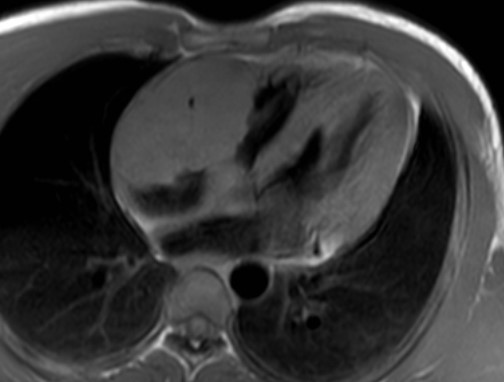

L'ecocardiogramma transtoracico (ETT) mostrava una grande massa isoecogena, non mobile, che occupava quasi interamente l'atrio destro, coinvolgeva la valvola tricuspide, che appariva funzionalmente stenotica, e si estendeva al tratto d’afflusso del ventricolo destro (Figura 1).

linfoma_cardiaco_1.jpg

Figura 1